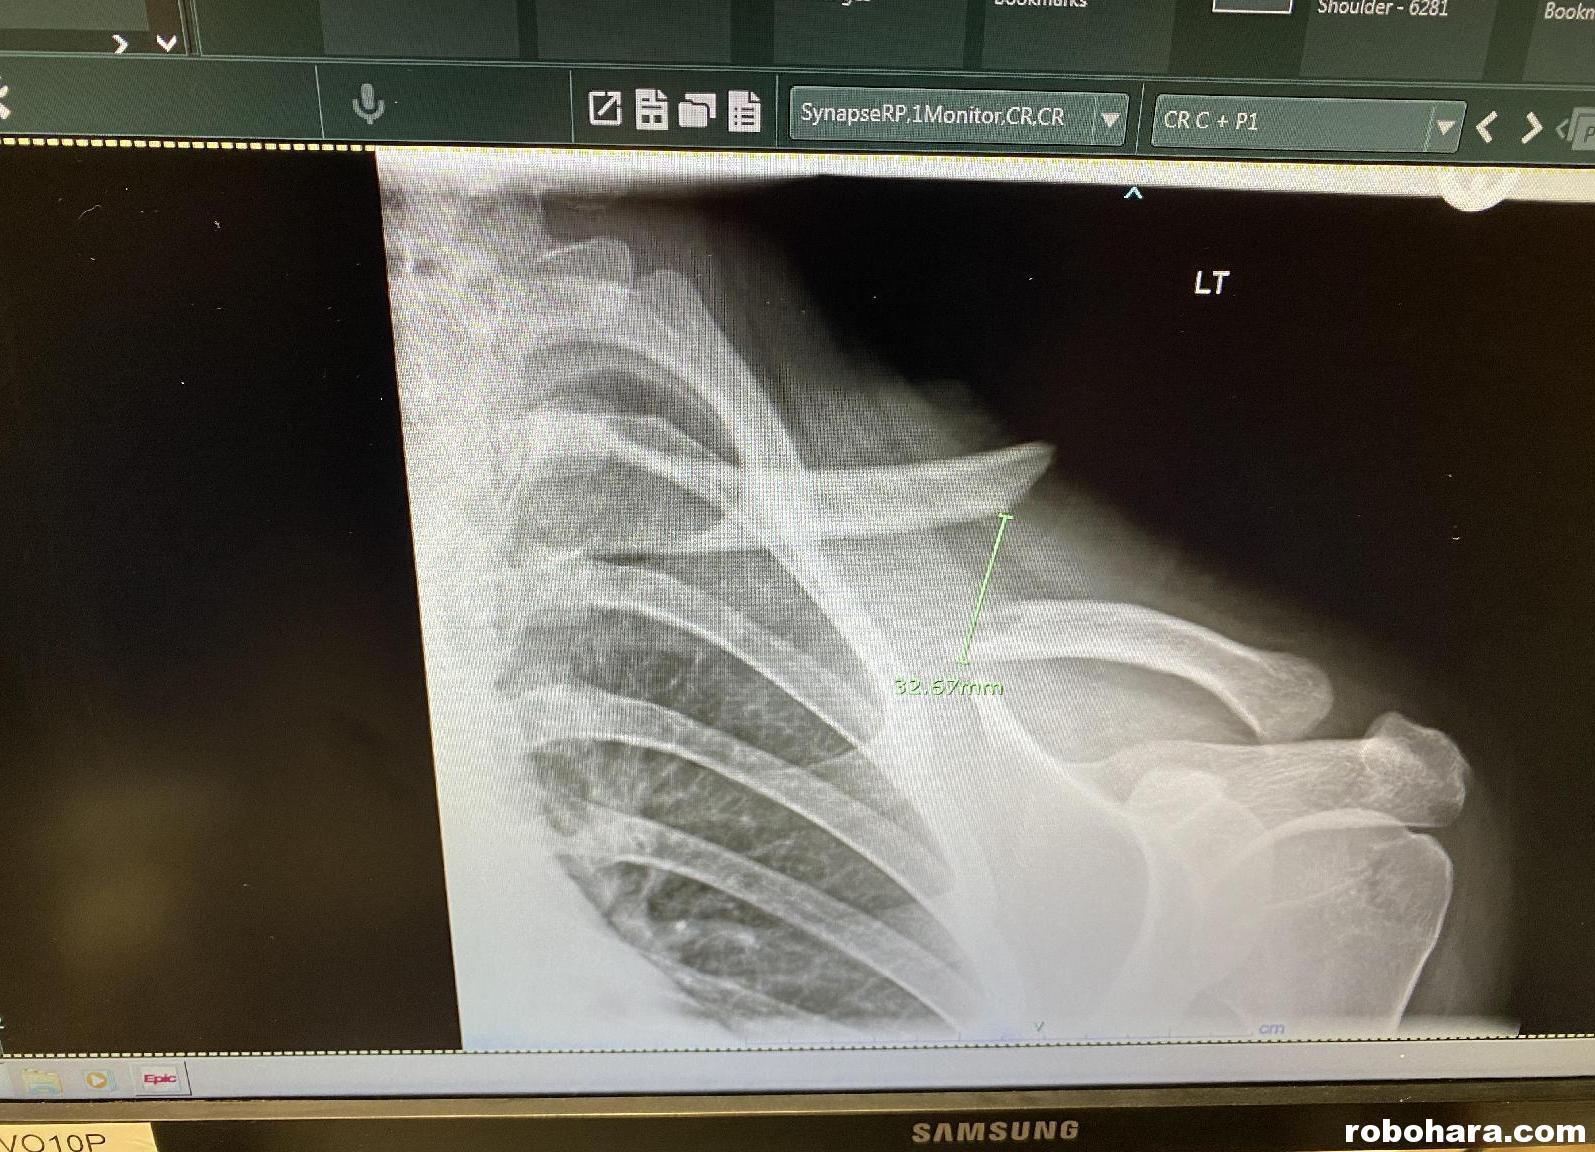

On Monday, Susan made an appointment for Morgan with a local pediatrician on Tuesday. (Morgan spent all of Monday on the couch, enjoying Doritos, Impractical Jokers, and Lortab.) At Tuesday’s appointment, the surgeon took more x-rays and explained to us that if the two ends of the collarbone were less than 20mm apart, they could be manipulated and coerced into reattaching with a sling. Morgan’s were nearly 35mm apart, which meant surgery was the best option. The surgeon that the waiting time for surgery was sometimes weeks, but that he’d had a cancellation for Wednesday, and although this felt like things were moving very quickly, if we were ready, he would pencil Morgan in for surgery at 8:30 a.m. on Wednesday.